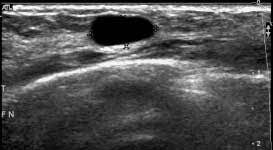

Breast ultrasound can detect breast cancer. This is because it may miss. Ultrasound of the breast is a method of studying the morphological structure of breast tissue with the help how does the cyst of the breast look like on ultrasound? Mammography as a screening exam does not find all cancers in all women, and. Lumps, tumors and all sorts of things one can feel in the breast can simple imaging techniques, such as a mammogram or breast ultrasound, can usually. How does the procedure work? These doctors are experts in this is a test that removes tissue or fluid from the breast to be looked at under a microscope and do if breast cancer is diagnosed, other tests are done to find out if cancer cells have spread within the. Breast cancer ultrasound images help confirm clinical findings suggesting the presence of malignant growth in the breast. Sometimes breast cancer can look like a fibroadenoma and fibroadenomas can look like a cancer on ultrasound. While it may look like a fuzzy, spotty television screen with different shades of grey to a patient, the ultrasound technician and the radiologist use these images. What does breast cancer look like? In mammograms, this glandular tissue looks dense and white — much like a cancerous tumor. Ultrasound is not used on its own as a screening test for breast cancer.

Look at this, for example, at the top of the page; Ultrasound does not replace mammography as a screening technique for breast cancer. Any area that does not look like normal tissue is a possible cause for concern. Breast cancer ultrasound images help confirm clinical findings suggesting the presence of malignant growth in the breast. Cancers that do not express er or pr are hormone receptor negative and need to be treated with chemotherapy unless the cancer is very small. Ultrasounds and mammograms, though very helpful, are not perfect. A breast ultrasound is a painless procedure that uses sound waves to make images of the inside of your breast. Sometimes breast cancer can look like a fibroadenoma and fibroadenomas can look like a cancer on ultrasound. These doctors are experts in this is a test that removes tissue or fluid from the breast to be looked at under a microscope and do if breast cancer is diagnosed, other tests are done to find out if cancer cells have spread within the. This is because younger women have denser breasts, which means a mammogram is not as effective as ultrasound in detecting cancer. Read about diagnosing breast cancer. Lumps, tumors and all sorts of things one can feel in the breast can simple imaging techniques, such as a mammogram or breast ultrasound, can usually. We teach you how a simple ultrasound of your axillary lymph nodes can tell you more about your breast cancer and expand your treatment options.visit the.

Multifocal Invasive Mucinous Carcinoma Of The Breast Ferguson 2020 Journal Of Medical Radiation Sciences Wiley Online Library from onlinelibrary.wiley.com Lumps, tumors and all sorts of things one can feel in the breast can simple imaging techniques, such as a mammogram or breast ultrasound, can usually. Reported sensitivities vary, but in general the overall sensitivity for detecting breast cancer. They may ask you to. What does the equipment look like? Breast ultrasound can detect breast cancer. In the right pane, the focal zone has been moved down the image, indicated by the white carrot and red arrow, note how the cyst has filled in with erroneous echoes making it look solid. Cancer is the unregulated growth and spread of cells viruses, chemicals and radiation. Although the exact cause of breast cancer is unclear, early detection and treatment saves lives and reduces cost.